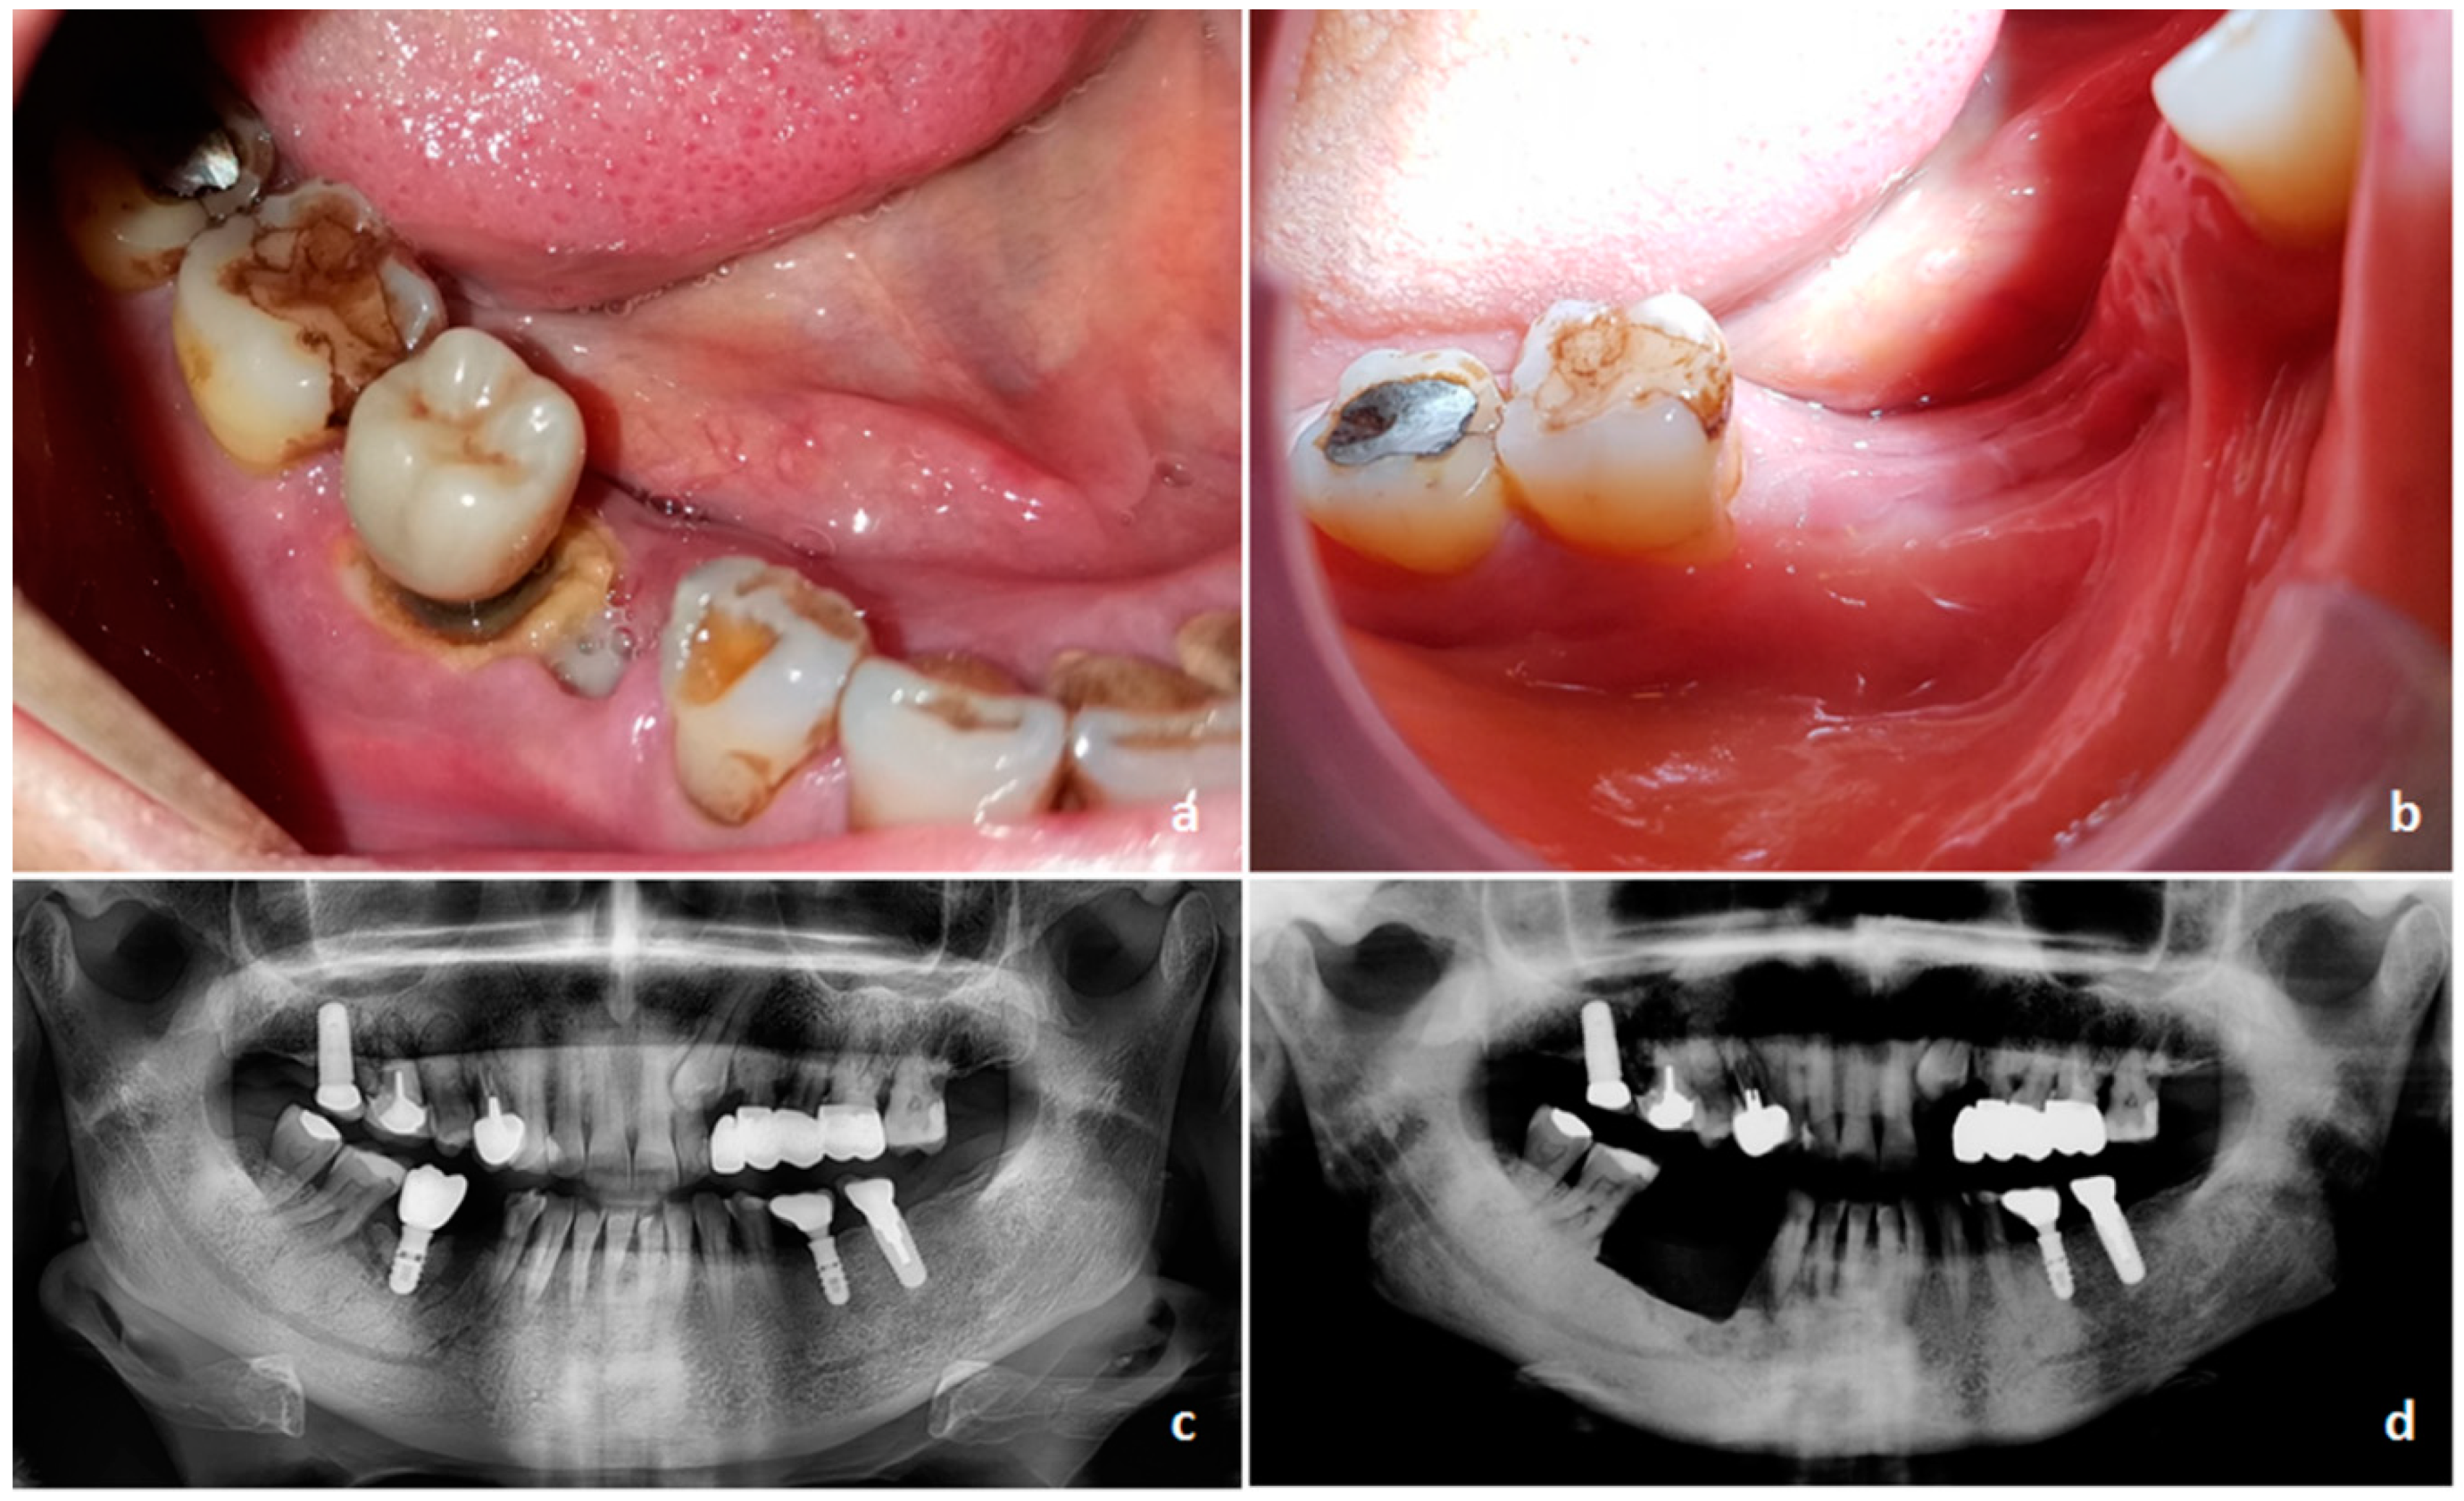

- Ruggiero, S.L.; Dodson, T.B.; Fantasia, J.; Goodday, R.; Aghaloo, T.; Mehrotra, B.; O’Ryan, F. American Association of Oral and Maxillofacial Surgeons Position Paper on Medication-Related Osteonecrosis of the Jaw—2014 Update. J. Oral Maxillofac. Surg. 2014, 72, 1938–1956. [Google Scholar] [CrossRef]

- Khan, A.A.; Morrison, A.; Hanley, D.A.; Felsenberg, D.; McCauley, L.K.; O’Ryan, F.; Reid, I.R.; Ruggiero, S.L.; Taguchi, A.; Tetradis, S.; et al. Diagnosis and Management of Osteonecrosis of the Jaw: A Systematic Review and International Consensus. J. Bone Miner. Res. 2015, 30, 3–23. [Google Scholar] [CrossRef] [PubMed]

- Fedele, S.; Bedogni, G.; Scoletta, M.; Favia, G.; Colella, G.; Agrillo, A.; Bettini, G.; Di Fede, O.; Oteri, G.; Fusco, V.; et al. Up to a quarter of patients with osteonecrosis of the jaw associated with antiresorptive agents remain undiagnosed. Br. J. Oral Maxillofac. Surg. 2015, 53, 13–17. [Google Scholar] [CrossRef] [PubMed]

- Khan, A.; Morrison, A.; Cheung, A.; Hashem, W.; Compston, J. Osteonecrosis of the jaw (ONJ): Diagnosis and management in 2015. Osteoporos. Int. 2016, 27, 853–859. [Google Scholar] [CrossRef] [PubMed]

- Fliefel, R.; Tröltzsch, M.; Kühnisch, J.; Ehrenfeld, M.; Otto, S. Treatment strategies and outcomes of bisphosphonate-related osteonecrosis of the jaw (BRONJ) with characterization of patients: A systematic review. Int. J. Oral Maxillofac. Surg. 2015, 44, 568–585. [Google Scholar] [CrossRef] [PubMed]

- Otto, S.; Tröltzsch, M.; Jambrovic, V.; Panya, S.; Probst, F.; Ristow, O.; Ehrenfeld, M.; Pautke, C. Tooth extraction in patients receiving oral or intravenous bisphosphonate administration: A trigger for BRONJ development? J. Cranio-Maxillofacial Surg. 2015, 43, 847–854. [Google Scholar] [CrossRef]